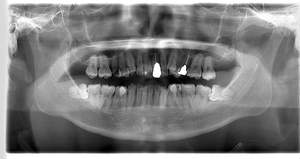

- 抜歯前写真(レントゲン)

| 年齢 | 20代・女性 |

|---|---|

| 主訴 | 左下親知らずがたまに痛み、できれば痛くなく抜きたい |

| 親知らずの生え方 | 完全に埋まっている、横向きに生えている |

| 抜歯時間 | 50分 |

| 費用 | 約8,000円(保険診療、CT代含む) |

| 抜歯内容 | 左下親知らずが横向きになって半分埋まっている状態だったため、麻酔を行い、親知らずの奥の歯ぐきに切開をいれ、歯が囲んでいる骨を削り、歯の頭の部分を削って出し、その後根の部分に器具をかけて抜歯しました。 親知らずが一部神経に近い部分があったため、術後に麻痺が出る可能性がありました。このケースでは事前にCTを撮影し、歯の位置、根の方向、神経との距離を確認していたため、幸い麻痺が出ることはありませんでした。 術後1週間経過して糸取りをして治療は終了となりました。抜歯後3日間は腫れと痛みで大変だったが、糸取りをする頃には痛みも腫れも無くなったと患者さまも喜んでおられました。 |